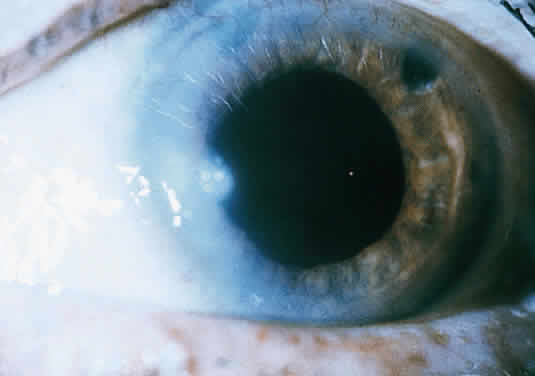

The more peripheral marginal infiltrate is sterile and is caused by a hypersensitivity reaction to the exotoxin or the bacterial antigens of S. aureus.35,36 The peripheral infiltrates usually are associated with blepharitis or conjunctivitis and frequently begin in the areas where the lid margins cross the limbus (at 2-, 4-, 8-, and 10-o'clock positions). The lesions often have a typical clinical appearance characterized by one or more small, well-circumscribed anterior stromal infiltrates, with a lucid interval between them and the limbus (Fig. 3). Although the epithelium is usually intact, it may break down, leading to ulceration, scarring, and neovascularization.